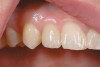

Figure 16  Replacement of the maxillary lateral incisor with a CAD/CAM zirconium abutment and a zirconium/ceramic crown.

Figure 16